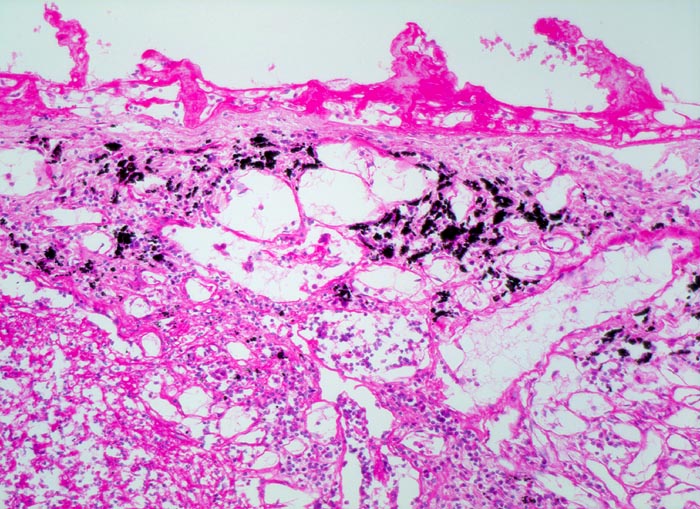

Regelmässig entwickelt sich eine Begleitpleuritis. In seltenen Fällen tritt ein Pleuraempyem, eine hämatogene Streuung (Pneumokokkenmeningitis, ulzeropolypöse Endokarditis, Arthritis oder Osteomyelitis), eine intrapulmonale Abszedierung oder eine chronische karnifizierende Pneumonie als Komplikation einer Lobärpneumonie auf.